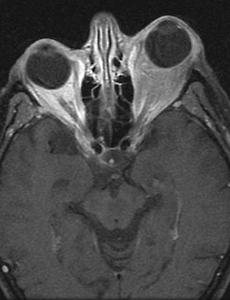

하지 정맥류가 눈에 발생하는 경우, 안와 정맥류, Orbital Varix, Orbital varices 안와 정맥류는.. 매우 드물게 발견되는 질환으로, 만성적인 안구 돌출의 원인중의 하나 입니다. 이때 안구 돌출이란 항상 안구가 돌출되는 것이 아닌, 간헐적인 안구 돌출(intermittent proprolapse)로써, 복압 상승으로 유발되는 간헐성 안구 돌출의 90%를 차지한다고 알려져 있습니다. 주로 아동기와 청소년기에 안구 돌출을 초래하며, 복압이 상승하여, 경정맥압이 상승하는 경우 뚜렷한 안구돌출을 관찰할수 있습니다. 발살바법을 시행하거나, 울고난뒤, 배에 힘을 주고 나면, 복압이 상승하고, 목의 정맥압이 상승하여, 정맥류속의 혈류가 저류되면서 정맥류의 크기가 커지게 되는 원리입니다. 안와 정맥류는 주로 단안에서 발생하며 때로는 같은쪽 얼굴이나 눈꺼풀, 코안, 입안에서도 비슷한 정맥류 병변을 관찰.. 2018. 9. 9.